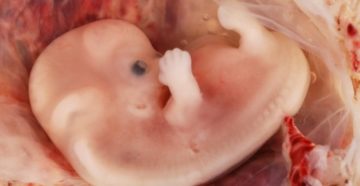

8 неделя беременности – что происходит С эмбриональной точки зрения этот период считается только шестой…

Причины замершей беременности на 8 неделе ВАЖНО! Для того, что бы сохранить статью в закладки,…